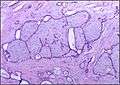

Fibroadenoma Histology (H&E). The image demonstrates intracanalicular morphology (top right) and pericanalicular morphology (bottom left)

Histopathologic image of breast fibroadenoma. Core needle biopsy. Hematoxylin & eosin stain.